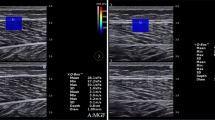

To ensure that the muscles and fascia are at rest, the subjects were allowed to have a 5 min rest before testing. Then, the subjects were placed at appropriate posture, and ultrasonic gel was applied to the skin around the marked location. Under the B-mode image, the probe was placed perpendicular to the skin and slightly adjusted parallel to the upper tendon muscle fibers to obtain a clear image. Once the probe orientation was aligned with the direction of the muscle fibers, we switched to E mode to quantify the shear modulus of the upper TLF (Fig. 2). The size of the region of interest (ROIs) is set to match the thickness of the TLF shallow (a variable range is chosen to achieve a larger area and to keep the border of the ROIs at a certain distance from the upper subcutaneous tissue and the lower muscles17).Three measurements were taken for each measurement point, and the measurements were averaged. In addition, to avoid the influence of abdominal fluctuation caused by breathing, we specifically save the image at the end of expiration to ensure the consistency of test results.